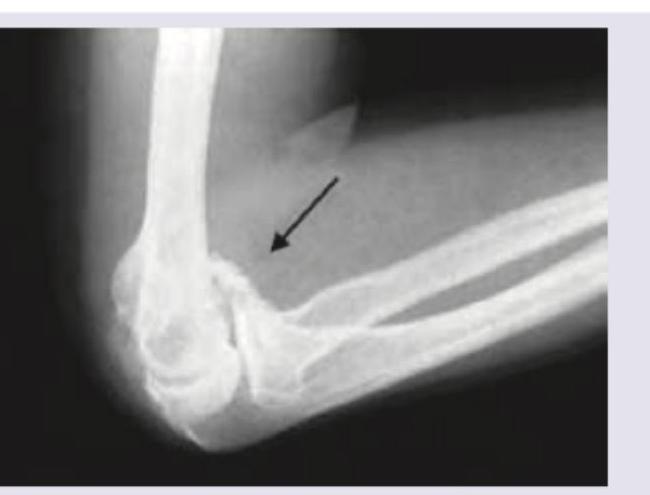

Explanation: **Needle biopsy** - **Needle biopsy** is generally **contraindicated** in cases of suspected or confirmed osteosarcoma due to the risk of **tumor seeding** along the biopsy tract or increasing the risk of metastasis. - Diagnosis is typically established via **open biopsy** to obtain a larger and more representative tumor sample for histopathological analysis. *Elevated ESR* - An **elevated Erythrocyte Sedimentation Rate (ESR)** is a common finding in many inflammatory conditions and malignancies, including osteosarcoma. - It reflects the body's generalized inflammatory response to the tumor. *Increased uptake in bone scan* - **Increased uptake** in a **bone scan** (using technetium-99m) is characteristic of osteosarcoma due to the tumor's high **osteoblastic activity** and increased bone turnover. - This increased metabolic activity leads to increased radionuclide accumulation in the affected area. *Appears 2 weeks postinjury* - A fracture or minor injury can sometimes be the initial event that brings an underlying osteosarcoma to clinical attention, as the tumor can **weaken the bone** making it more susceptible to fracture. - However, the image shows a lytic lesion, which is typical of osteosarcoma, and not necessarily a fracture appearing 2 weeks post-injury; the tumor itself may have been developing for a longer period.